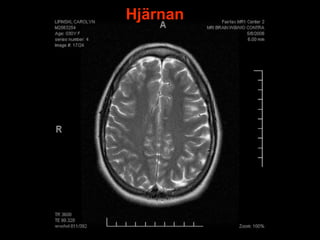

Hjärnan

Utvecklas bakifrån och framåt.

Väger cirka 1,5 kg.

I pannloben sitter hela personligheten.

Står för ca 1/4 av kroppenenergibehov.

Skyddas av;

Skallbenet

Hjärnhinnor

Cerebrospinalvätska

6